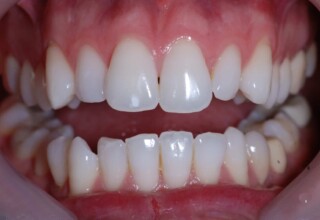

Αποκατάσταση διαστημάτων μεταξύ κεντρικών και πλαγίων τομέων

Τα διαστήματα έχουν δημιουργηθεί κυρίως λόγω των στενών πλαγίων. Μετά την ολοκλήρωση της ορθοδοντικής θεραπείας τα διαστήματα “έκλεισαν” με την τοποθέτηση δύο αποκαταστάσεων σύνθετης ρητίνης.